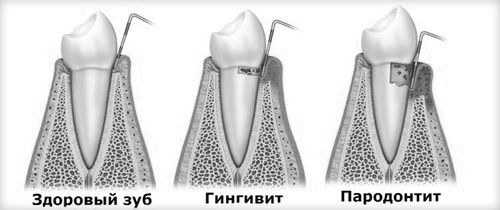

- гінгвіт, що супроводжується набряком, появою кровоточивості і синюшности ясен, і його запущена форма парадонтит, при якій запальний процес призводить до оголення шийок зубів, їх підвищеної рухливості і формування гнійних виділень,

Гінгівіт, пародонтит

При таких проблемах болю можуть бути досить інтенсивними, і до звернення до лікаря пацієнт може скористатися знеболюючими препаратами для зняття симптоматики. Однак похід до стоматолога відкладати не можна, інакше можуть послідувати небезпечні ускладнення.

Отже, гінгвіт і пародонтит зазвичай є наслідком неправильного догляду за ротовою порожниною і формування зубного каменю, саме тому лікування починають з видалення утворень і видачі детальної інструкції по правильній гігієні ротової порожнини. Індивідуальний курс лікування зазвичай має на увазі використання протизапальних продуктів - гелів Метрогил Дента, Метродент, Асепта тощо. Також лікарі прописують лікувальні зубні пасти (наприклад, Пародонтакс) і процедури по полоскання ротової волості антисептичними розчинами (Хлоргексидин, Марамістін і т.д.).

Пародонтит, як більш складна форма проблеми, вимагає додаткових заходів. Зазвичай курс терапії включає в себе прийом антибіотичних препаратів, а також процедури по очищенню гнійних кишень (це хірургічна методика з подальшим ушиванням тканин для закриття оголених коренів). Таким чином, повністю від болю вийде позбутися тільки в тому випадку, якщо буде усунуто саме запалення. В рамках всього курсу лікування лікарем призначається коректний анальгетик.